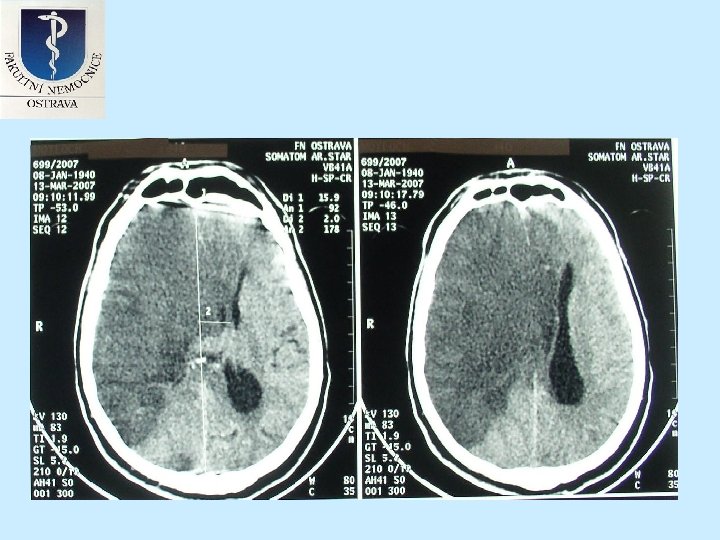

Indikátory mortality u pacientů s dekompresní hemicraniectomií • 5. Velikost ischemického ložiska v cm 3 zjištěné planimetrickou metodou v den operace. • 6. Velkost přetlaku střední čáry na CT snímku v den operace. • 7. Výsledný klinický stav zjištěný pomocí m. Rankinovi škály v době propuštění z nemocnice.